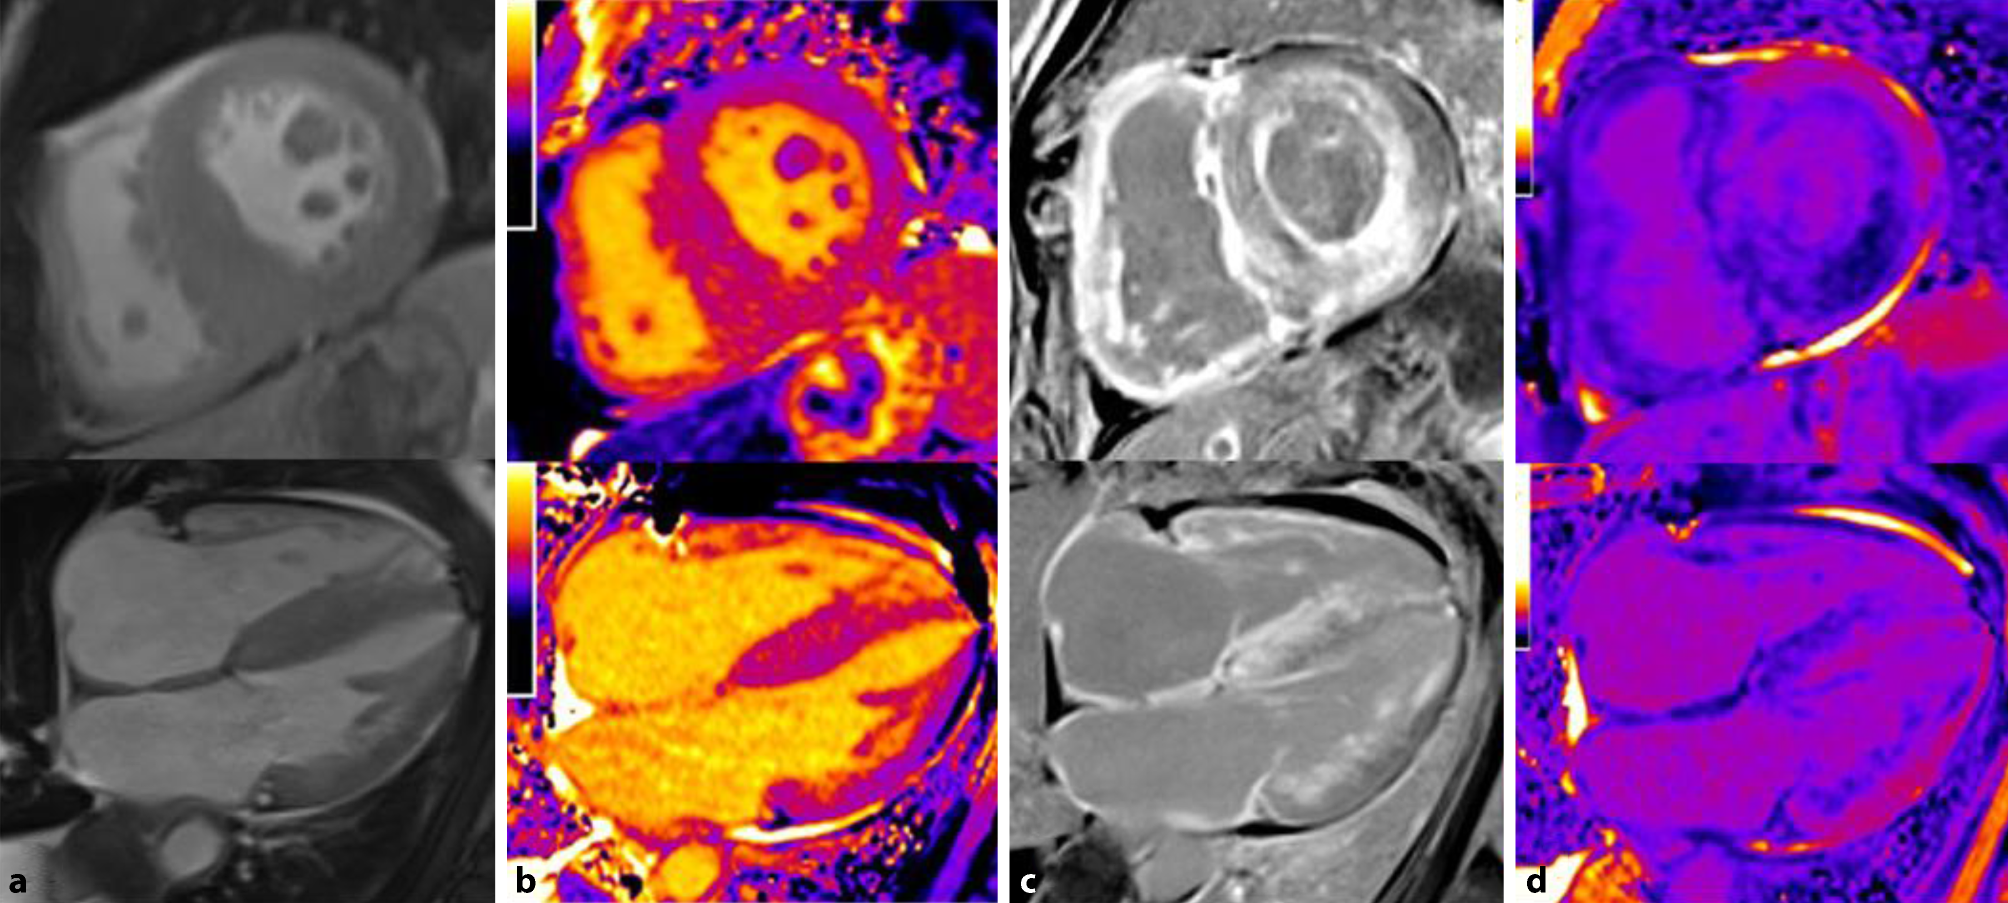

At the structural level, ATTR amyloidosis is more commonly characterized by markedly asymmetric LV hypertrophy, while AL amyloidosis often shows less pronounced, symmetric, concentric LV hypertrophy (Fig. 3a); however, the absence of LV hypertrophy does not preclude cardiac amyloidosis [75].

Fig. 3

Magnetic resonance tomography in a patient with cardiac transthyretin amyloidosis. Top row: short axis view. Bottom row: four-chamber view. a Functional cine imaging showing pronounced left ventricular hypertrophy. b T1 mapping showing globally increased T1 relaxation times of 1180 ± 38 ms. c Biventricular late gadolinium enhancement with subendocardial enhancement showing characteristic, global patchiness mostly in the basal segments of the myocardium. d Extracellular volume (ECV): globally increased ECV of 58.4%, estimated according to the formula: ECV = (1 − hematocrit) × [1/post-contrast T1 myocardium − 1/native T1 myocardium]/[1/post-contrast T1 blood − 1/native T1 blood]

Late gadolinium enhancement (LGE; Fig. 3c) can be used to differentiate cardiac amyloidosis from other pathological changes. In advanced stages of amyloidosis, accumulation of the extracellular contrast agent gadolinium in the expanded interstitial compartment results in the typical diffusely speckled LGE pattern that can be complemented by focal, subendocardial LGE (subendocardial ring). The ATTR amyloidosis subtype often shows transmural LGE, whereas AL amyloidosis frequently demonstrates a subendocardial distribution pattern [76]; however, the enhancement pattern varies considerably, especially in the early stages of the disease; thus, cases of biopsy proven cardiac amyloidosis without pathological LGE have been reported [76].

The newer mapping methods enable quantification of magnetic tissue properties using myocardial T1 relaxation times before and after administration of the contrast agent, which also allows estimation of the extracellular volume (ECV) (Fig. 3b; [77]). While the native T1 time constitutes a composite myocardial signal from myocytes and the interstitium and cannot be used to completely differentiate the underlying disease process (fibrosis, edema, amyloid and/or myocyte necrosis) [78], ECV represents the signal of the extracellular space. A validation study demonstrated that ECV according to CMR correlates well with histological findings based on cardiac biopsies [79].

Increases in both native T1 relaxation time of the myocardium [78, 80, 81] and ECV provide high diagnostic accuracy for cardiac amyloidosis in patients with high pretest probability [82, 83] and enable a prognosis assessment. Overlap with other diseases that also involve LV hypertrophy limit the diagnostic significance of ECV, however [84]. Furthermore, mapping results depend on the device, field strength, and the sequence used, among other aspects, [85] and generally accepted thresholds for ECV and native T relaxation time have not yet been established. Nevertheless, both methods can be used to judge the severity of myocardial involvement and to monitor responses to treatment. [79].